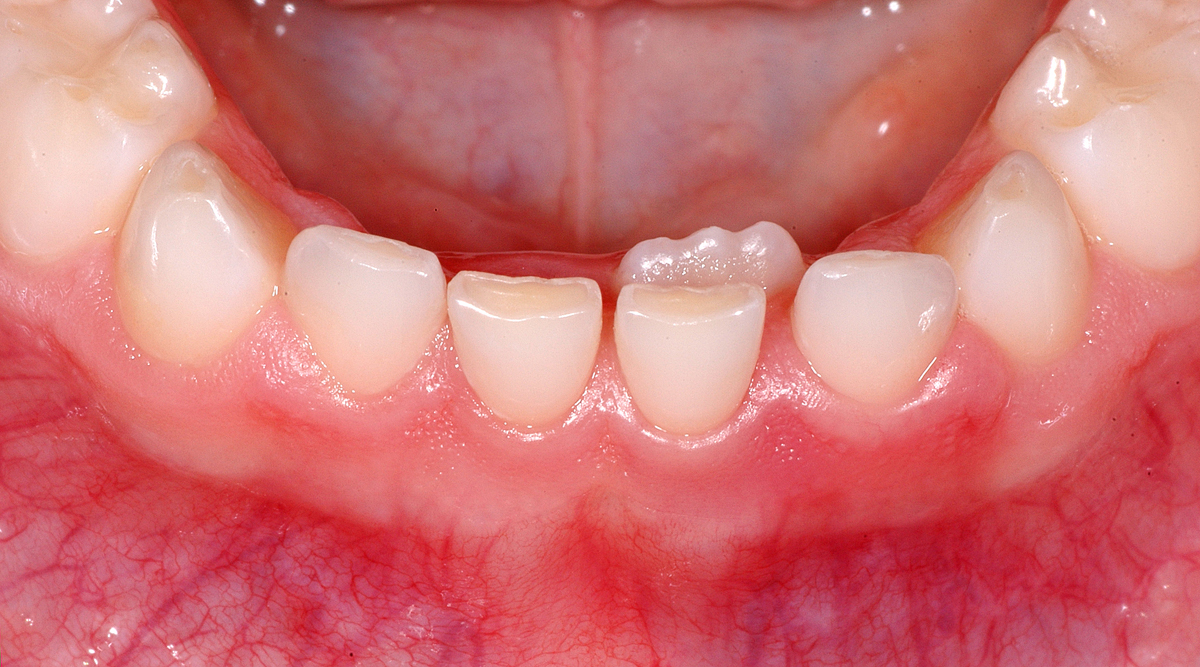

Anbei zeige ich einen ganz ähnlichen Fall, bei dem aber die seitlichen Schneidezähne im Unterkiefer betroffen sind.

Der Patient ist knapp 8½ Jahre alt, das Bild zeigt den Zustand, wie er sich bei der Erstkonsulation präsentierte. Die bleibenden Zähne sind schon sehr weit, fast ganz, durchgebrochen. Die Milchzähne sind noch komplett fest. Daher haben wir uns entschieden, die Milchzähne demnächst zu entfernen, damit die bleibenden so gut als möglich an die «richtige» Stelle kommen können.

Oft genügt der Zungendruck allein, damit sich die bleibenden Zähne im Laufe der Zeit in die Zahnreihe stellen. Wenn die bleibenden Zähne noch früher im Durchbruch sind, ist es in der Regel eher so, dass sie an die richtige Position kommen. Im vorliegenden Fall wird sich zeigen müssen, ob die Natur diese «Fehlstellung» von selbst komplett zu korrigieren vermag; immerhin ist genügend Platz vorhanden. Die Entfernung zu einem schon etwas früheren Termin wäre hier sicher hilfreich gewesen.